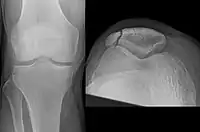

Some people have a normal bipartite patella or two-part patella which can appear as a fracture. The fragment is usually seen in the top outer corner of the patella and can be distinguished from a fracture by being present in both knees.[6]

The patella can break in various ways depending on the way it is injured, and into two or more pieces.[1] Types include transverse, the most common, with one fracture line;[5] marginal; osteochondral; and the rare vertical type, or stellate, where a direct compression force gives rise to a comminuted pattern.[5][7] Patella fractures can be further classified as displaced, where the broken ends of bone do not line up correctly and separate by more than 2mm, or undisplaced and stable where pieces of bone remain in contact with each other.[1][7] If fragments of patella bone stick out from the skin it is known as an open patella fracture, and closed if the overlying skin is intact.[1]